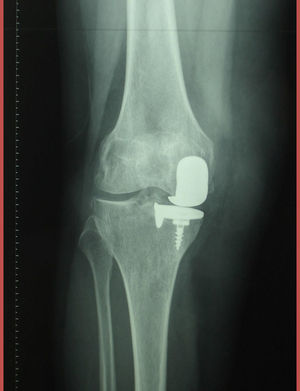

Mujer de 72años, con antecedentes de artroplastia unicameral de rodilla derecha desde hacía 12años, que acude a nuestra consulta por dolor en dicha rodilla de 6meses de evolución, sin fiebre ni síntomas sistémicos. En la exploración física se objetivó tumefacción de dicha rodilla. La radiografía mostró prótesis parcial en el compartimento medial, sin alteraciones (fig. 1). Se realizó artrocentesis, obteniendo un fluido oscuro (fig. 2), con 150 células (75% polimorfonucleares), glucosa 90mg/dl, proteínas 2mg/dl. El cultivo del líquido articular fue negativo. Con la sospecha de metalosis, la paciente fue derivada a la consulta de traumatología, y la prótesis fue sustituida por una prótesis total. Una muestra de tejido sinovial fue enviada a anatomía patológica, mostrando macrófagos con pigmento negruzco en su citoplasma y linfocitos (figs. 3 y 4). Actualmente la paciente se encuentra asintomática.

La metalosis se define como una corrosión debida a la erosión de los componentes metálicos, que producen partículas que inducen una reacción de hipersensibilidad. Generalmente es asintomática y la aparición de dolor o rigidez se debe al aflojamiento secundario de la prótesis1. Su sospecha puede surgir al apreciar zonas osteolíticas lobuladas con o sin aumento de los tejidos blandos adyacentes en la radiografía simple, debiendo realizarse diagnóstico diferencial con movilización aséptica de la prótesis y con artritis séptica2. Macroscópicamente aparece una pigmentación negruzca de la articulación junto con un líquido sinovial oscuro. Microscópicamente podemos apreciar partículas metálicas, ya sean libres o absorbidas por macrófagos, con un infiltrado linfocitario que sugiere una respuesta inmune3. El tratamiento consiste en el reemplazo de la prótesis y la realización de una sinovectomía con el fin de eliminar las partículas metálicas3.